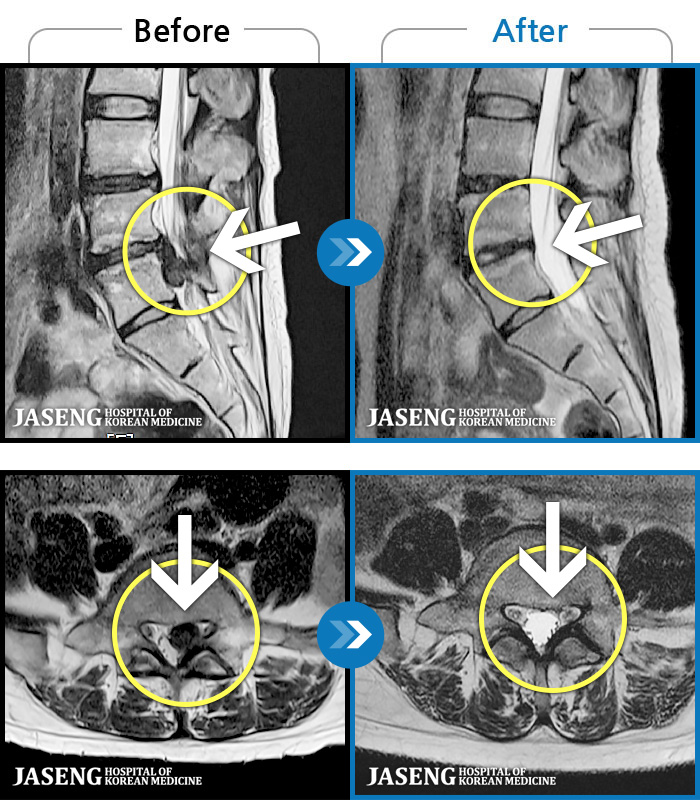

허리디스크

많이 본 사례

인천 · 조남훈 원장

계속 아파서 일을 일주일에 2번밖에 못해요.

촬영시기

2019.11.23 ~ 2023.12.15

2023.12.20